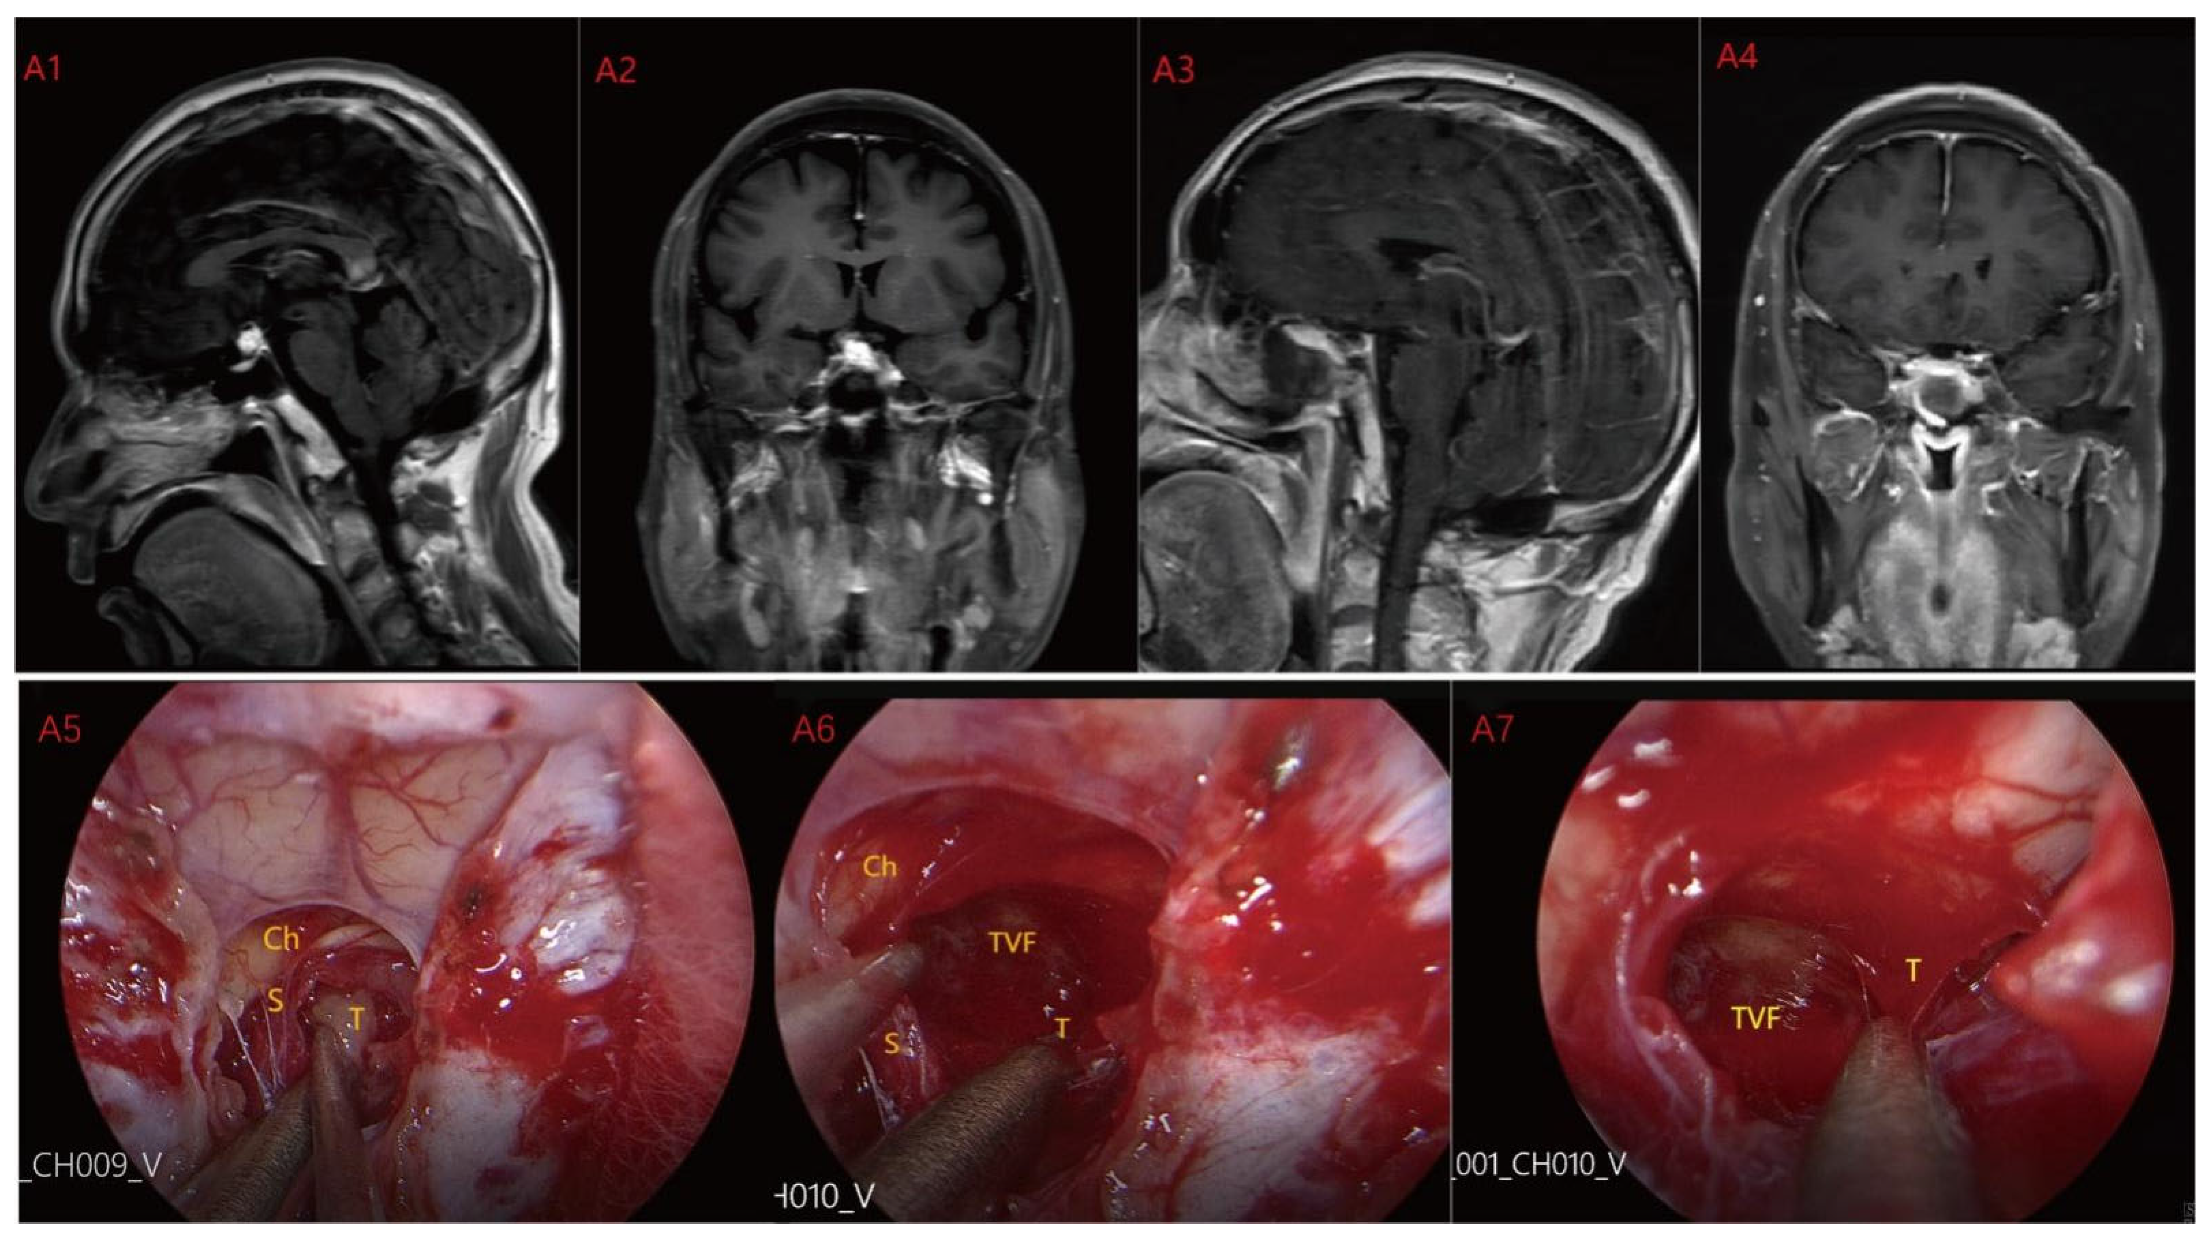

Based on MRI data and intraoperative findings from EEA, we classified PCPs into three types: (1) Type I: Suprasellar/intra-suprasellar (3V floor intact) type: most tumors originate from the segments of the pituitary stalk between diaphragma and infundibulum, as shown in Figure 1. (2) Type II: Suprasellar/intra-suprasellar (3V floor invasive) type: most of the tumors originate from pituitary stalk (PS), or infundibulum and median eminence (ME); the interface between tumor and 3V floor is not clear or has disappeared, and the tumor infiltrates into the bottom of the third ventricle, as shown in Figure 2 and Figure 3. (3) Type III: Intra-third ventricle type; most of the tumors originate from the infundibulum and ME, the tumor grows strictly inside the third ventricle, the 3V floor is intact and covered with arachnoid membrane, as shown in Figure 4 and Figure 5.

Figure 1.

Case 1: Type I: Suprasellar/intra-suprasellar (3V floor intact) type. The third ventricular floor (TVF) and mammillary bodies (MB) were not involved preoperatively (A1,A2). The EEA approach was chosen for surgery, and the TCPCA was used. Intraoperative photographs (A5) show the pituitary stalk (PS) and surrounding perforating vessels. The tumor was located lateral to the PS, and the pituitary stalk was kept intact during the operation. After most of the tumor was resected, the complete third ventricle floor could be seen (A6,A7). Finally, the tumor was completely resected (A3,A4) and the third ventricle floor was completely preserved. Ch = optic chiasm TVF = third ventricle floor T = tumor S = pituitary stalk.